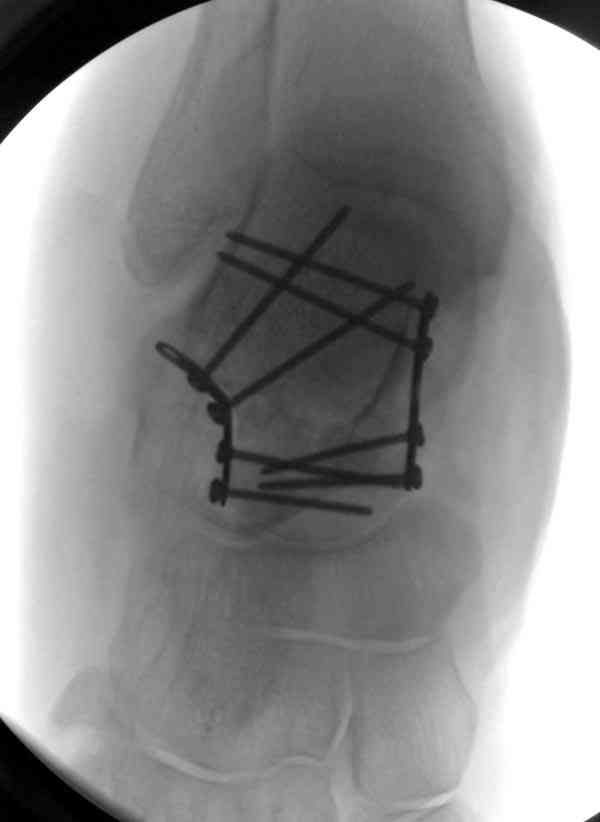

Решили не связываться с остеосинтезом, а сделать сразу берцово-пяточный блок. Снимки в приложении.

По завершении удлинения, наверно, заштифтуем.

Комментарии/критика приветствуются.